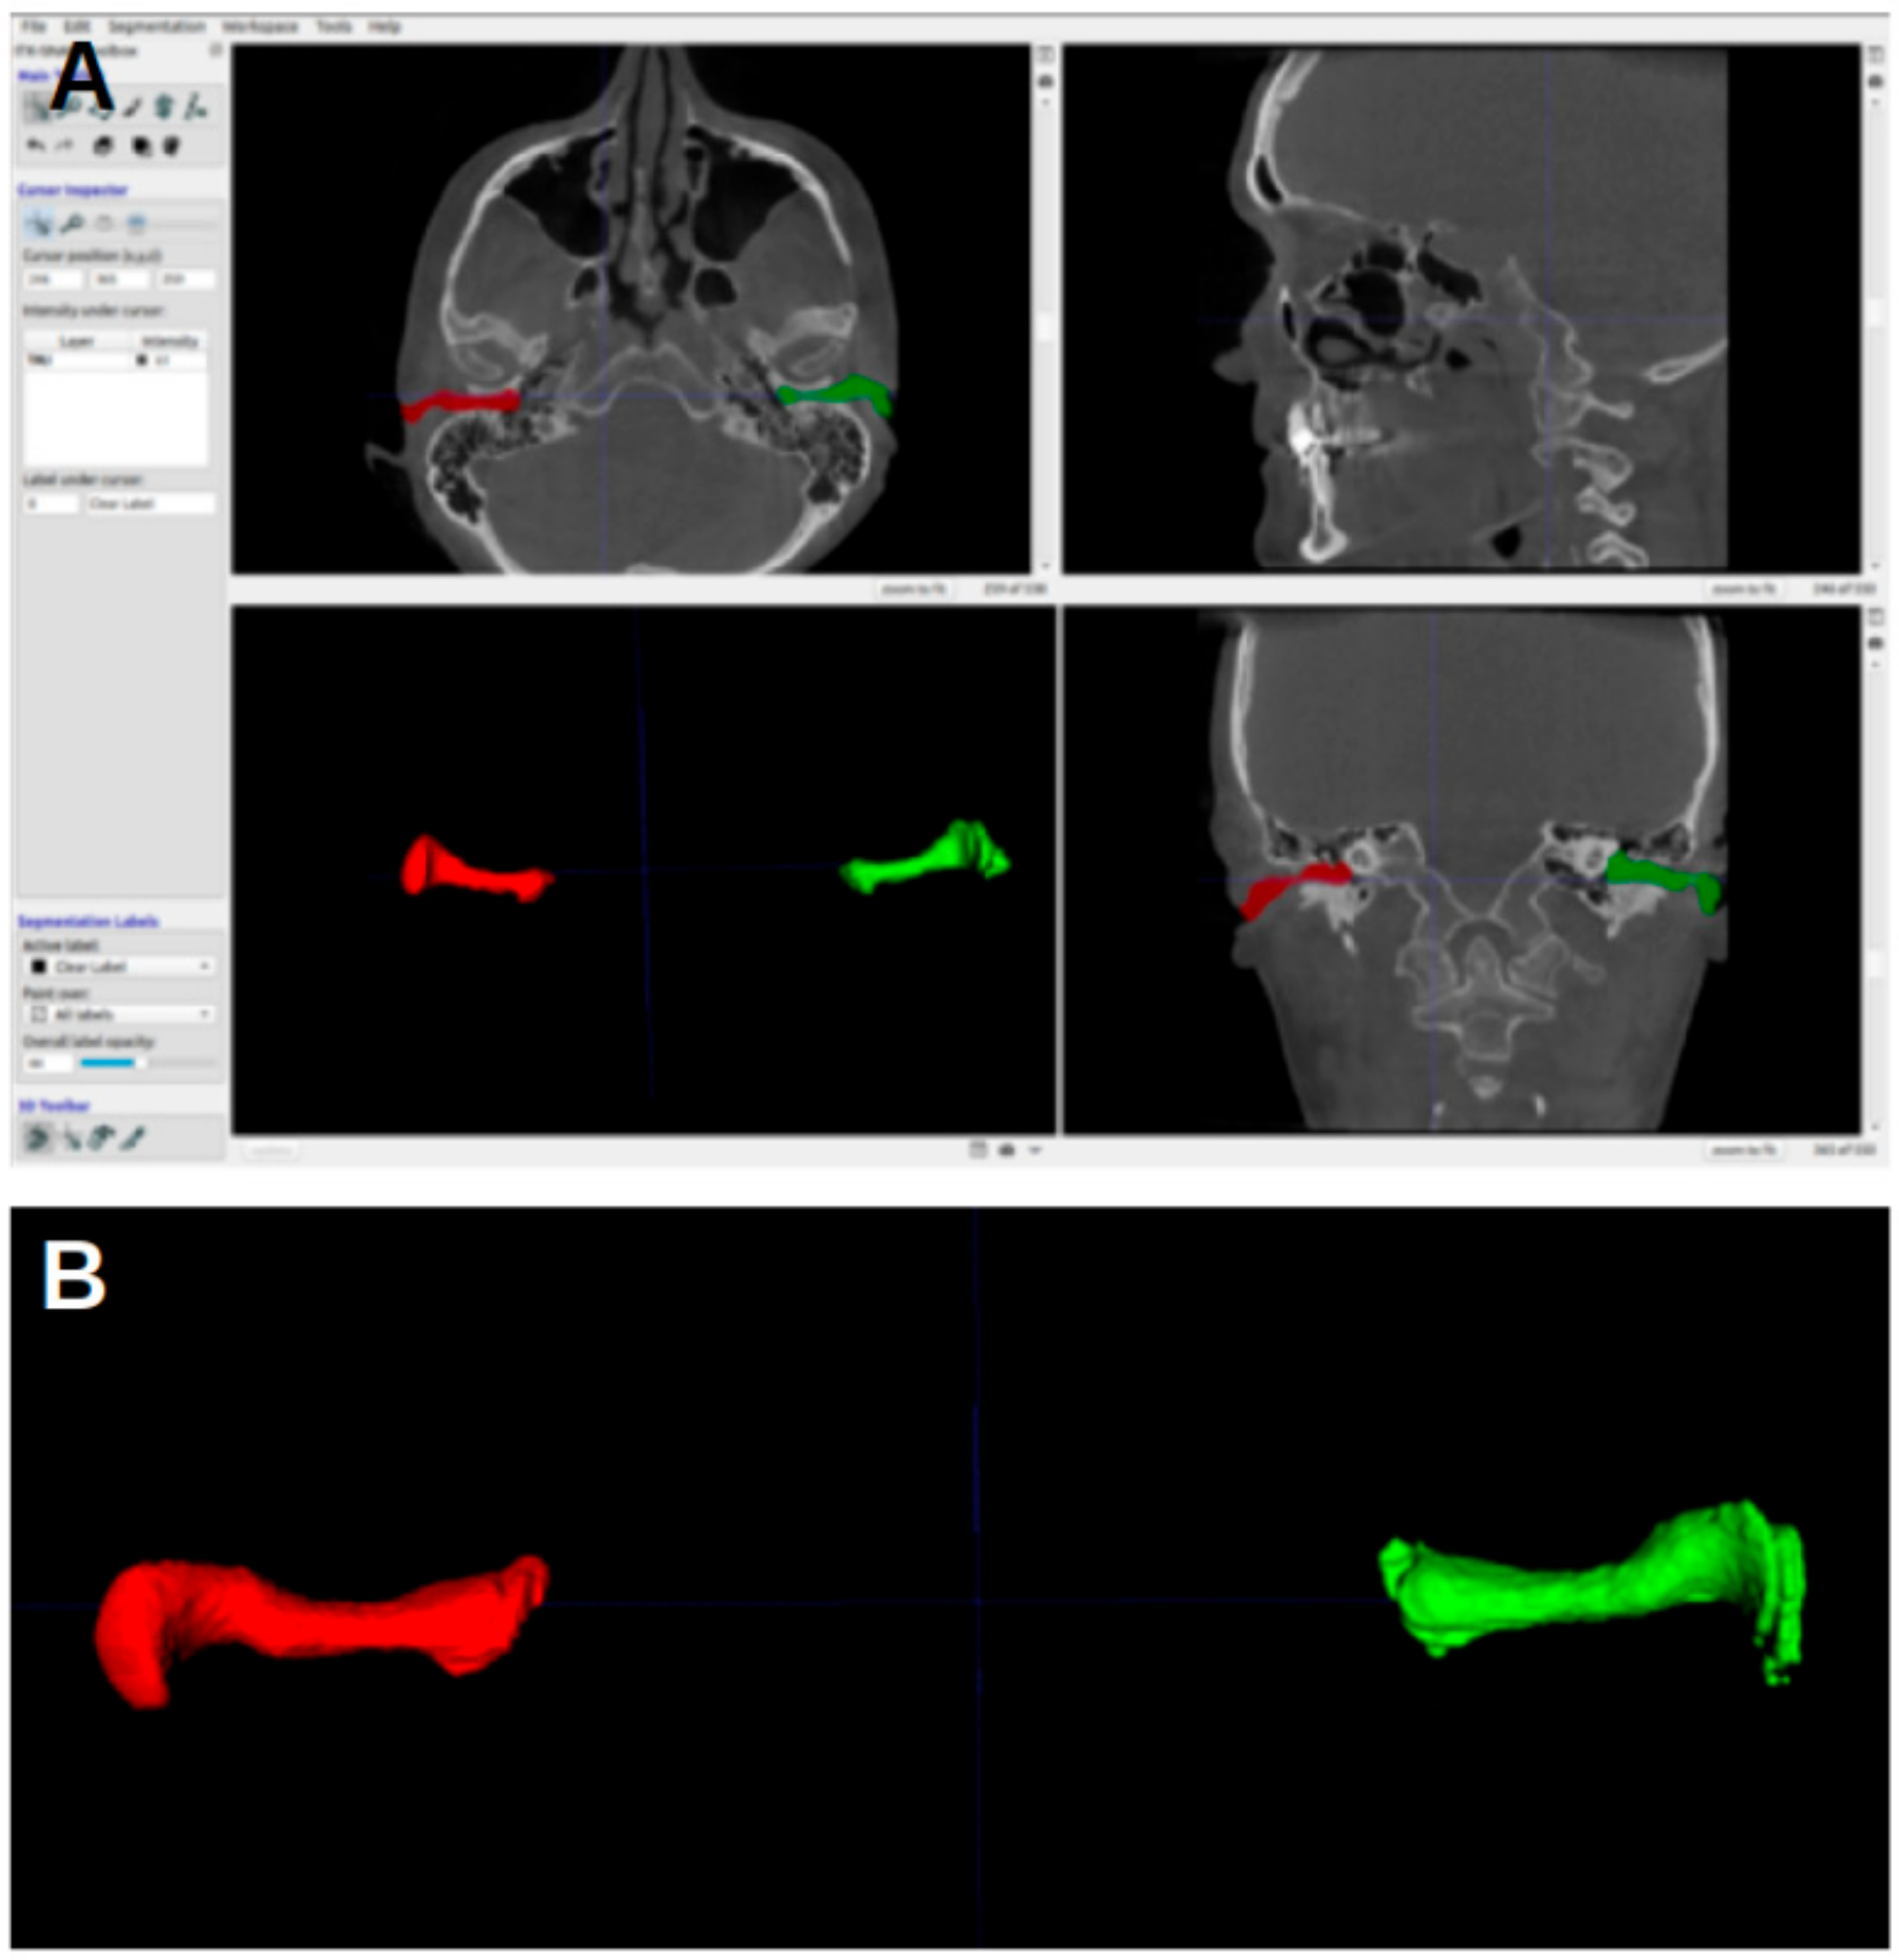

The CBCT images were represented on the computer as DICOM (Digital Imaging and Communication in Medicine) files. The CBCT images were analyzed using ITK-SNAP software, version 3.8, University of Pennsylvania, Philadelphia, PA, USA, (www.itksnap.org, (accessed on 17 June 2023)) [15]. The acoustic meatus were segmented using the “active contour segmentation mode”, which enabled ITK-SNAP to differentiate between different structures according to the grayscale of the image. The segmented acoustic meatus on the right side were labeled with a red color (label 1), and those on the left with a green color (label 2). Figure 1 shows an example of the segmentations.

Figure 1. Three-dimensional reconstruction of the acoustic meatus. (A) A representation in ITK-snap. (B) Coronal view of the segmentations of the right (red) and left (green) meatus, with the EAM flowing into the cauliflower-like shape representing the internal acoustic meatus.